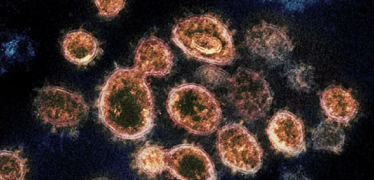

مادة تحمي من فيروس كورونا لمدة 90 يوما

باب أمل.. خلايا كامنة في دمائنا تقارع كورونا

دراسات: عقار هيدروكسي كلوروكين "لا يفيد" مرضى كورونا

الصحة العالمية: استخدام هذا الدواء قد يكون قاتلاً

أقرته اليابان.. رسميا "أول دواء" لعلاج لكورونا

دون فحوصات.. "طريقة علمية" للوصول إلى مصابي كورونا

تحذير عالمي: أزمة كورونا تعبث بالصحة العقلية للبشر

فيروس كورونا يمكنه الانتشار عن طريق "التكلم"

كندا تخطط لتصنيع لقاح صيني مضاد لكورونا

العلماء يكتشفون طريقة مفاجئة لانتقال الفيروس التاجي